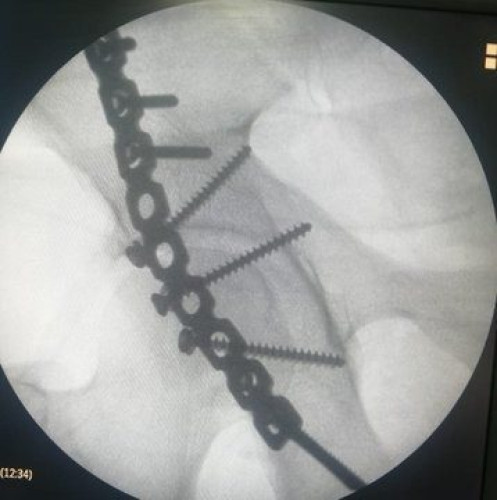

تعامل بنجاح فريق طبي في مستشفى القويعية العام مع حالة مصاب في حادث مروري تسبب له في كسور متعددة معقدة “كسور في الساق اليمنى، والحوض الأيمن “الجوف الحقي الأيمن”.

حيث تم اجراء عمل عملية لتثبيت الكسور، وكذلك تثبيت كسر الحوض الأيمن، بشريحة إعادة بناء مفصل الحقي المفصلي الأيمن، مع إعادة بناء محفظة المفصل، وقد تماثل المصاب للشفاء ولله الحمد وتحسنت حالته.